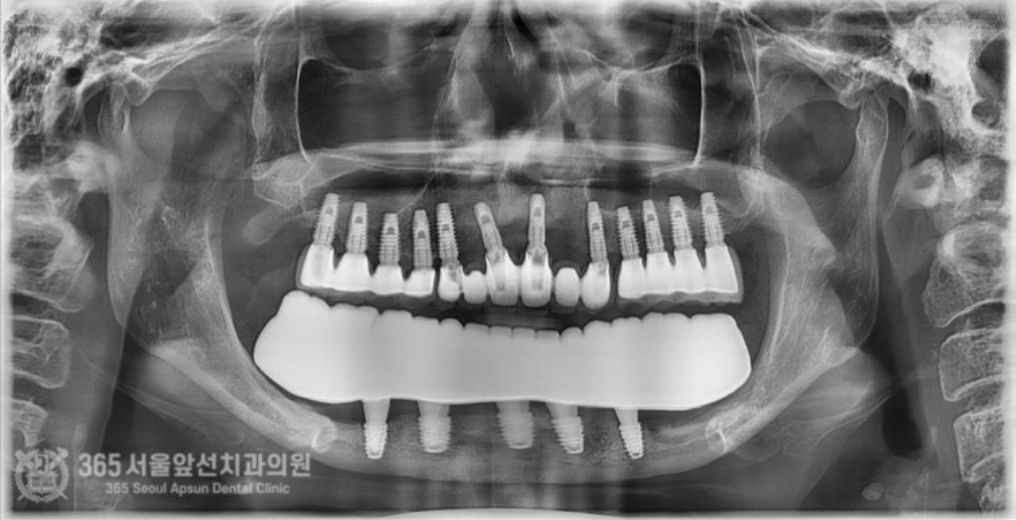

아래쪽에 임플란트 틀니를 썼었는데, 전체 임플란트 치료를 받고 싶어서 치과에 갔더니 뼈가 없어서 임플란트가 불가능하다고 판정받았어요. 촬영일시 : 2024.07.07. 처음 내원 당시 엑스레이 사진입니다. 촬영일시 : 2024.07.07. 사진에 노란색 표시를 한 곳이 신경관입니다. 보다시피 어금니 부위에는 뼈가 하나도 없습니다. 이 정도 뼈 상태라면 1000명의 환자분이 오신다면 그 중 단연코 1등으로 뼈가 안좋으신 상태 정도 됩니다. 기존의 임플란트는 제거를 해야하고, 이후 신경관을 피해서 5개의 임플란트를 식립하기로 했습니다. 촬영일시 : 2024.07.07. 수술 전 CT 사진으로 신경 구조물에 대한 정확한 사전 파악 후 수술에 들어갑니다. 왼쪽 아래턱 부위의 신경이 손상되지 않게 조심스럽게 수술을 진행했습니다. 오른쪽 아래턱 부위도 동일하게 신경이 손상되지 않게 조심스럽게 수술을 진행합니다. 기존 임플란트는 상태가 좋지 않아서 제거했습니다. 촬영일시 : 2024.07.07. 촬영일시 : 2024.11.16. 임플란트 수술 후 엑스레이입니다. 원하는 위치에 정확히 임플란트가 식립되었습니다. 임플란트가 뼈와 단단하게 굳으면 본을 떠줍니다. 정교한 보철물을 위해선 정확한 본뜨기 작업은 필수겠죠? 촬영일시 : 2024.11.16. 완성된 보철물입니다. 촬영일시 : 2024.11.16. 대략 4개월에 걸쳐 치료를 완료해드렸습니다. 환자분께서는 아주 만족하셨습니다. 정확한 임플란트 수술을 통해 신경 손상없이 성공적으로 마무리할 수 있었습니다 ㅎㅎ 촬영일시 : 2024.07.07. / 2024.11.16. 보철물 장착 전후의 입술 모습의 변화를 볼 수 있습니다. 입술이 볼록하게 지지받아서 자연스러운 안모로 변화했습니다. 촬영일시 : 2024.07.07. / 2024.11.16. 전후 구강내 사진입니다. 잇몸뼈가 많이 없으셔서 잇몸 부위를 핑크색이 나는 재질로 채워드렸습니다. 임플란트 불가능 판정을 받으셨던 환자분이신데 치료가 잘 마무리 되어 뿌듯했습니다 ㅎㅎ 신경관이 근접한 고난이도 임플란트 치료지만 충분한 경험과 지식이 있다면 치료가 가능하니 걱정 안하셔도 되겠습니다. 지금까지 365일 열린 가까운 서울대학교 치과병원을 지향하는 365서울앞선치과였습니다. 감사합니다. [ 치료기간 : 2024년 7월7일 ~ 2024년 11월 16일 ] ※ 365서울앞선치과의원의 모든 포스팅은 각 진료과 의료진이 직접 작성합니다. 365서울앞선치과의원 블로그의 임상 케이스 게시물은 환자분께 의학적으로 정확하고 상세한 정보를 드리기 위해 각 진료과 의료진이 직접 작성하며, 모든 증례 사진은 본원 의료진이 직접 시술한 증례를 촬영한 것으로, 의료법 제23조, 제56조에 의거하며 환자분의 동의를 얻어 포스팅에 사용하였습니다. 또한 해당 케이스는 본 환자분의 치료 결과이며, 환자 상태에 따라 치료의 결과는 달라질 수 있습니다. |